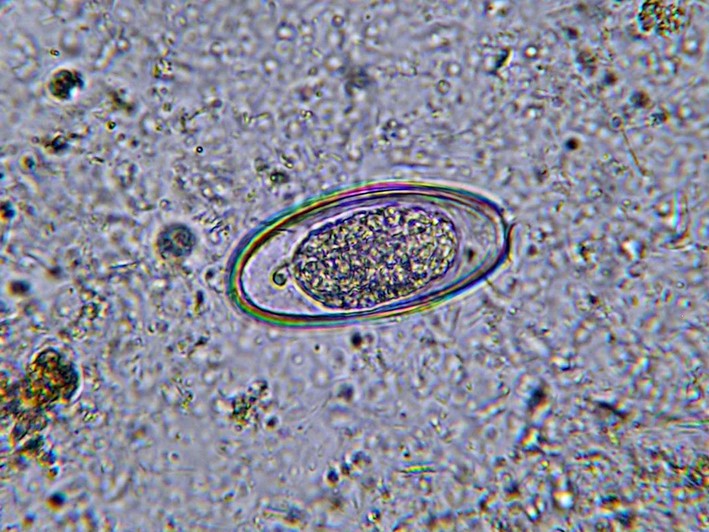

В одном глазу яйца остриц

Яйца остриц не различимы на глаз, имеют продолговатую форму и покрыты оболочкой. В момент откладывания они содержат уже начавший формироваться зародыш.

Яйца остриц под микроскопом (фото): какого цвета и величины

Яйца глистов очень мелкие по размерам, их можно беспроблемно обнаружить только под микроскопом.

Воспользовавшись особым оборудованием можно увидеть продолговатые или округлые формы. Они, ассиметричные имеют двухконтурные оболочки. Окрас белый, приближенный к серому цвету.

Микроскопический размер яиц позволяет рассмотреть их только под сильным увеличением. Как выглядят яйца остриц под микроскопом? Фото ниже даст ответ на этот вопрос. Лаборант, исследуя биоматериал, наблюдает следующую картину. Форма яйца овальная, причем одна сторона более выпуклая. Внутри находится вытянутая личинка. Оболочка яйца состоит из двух контуров и полностью бесцветна.